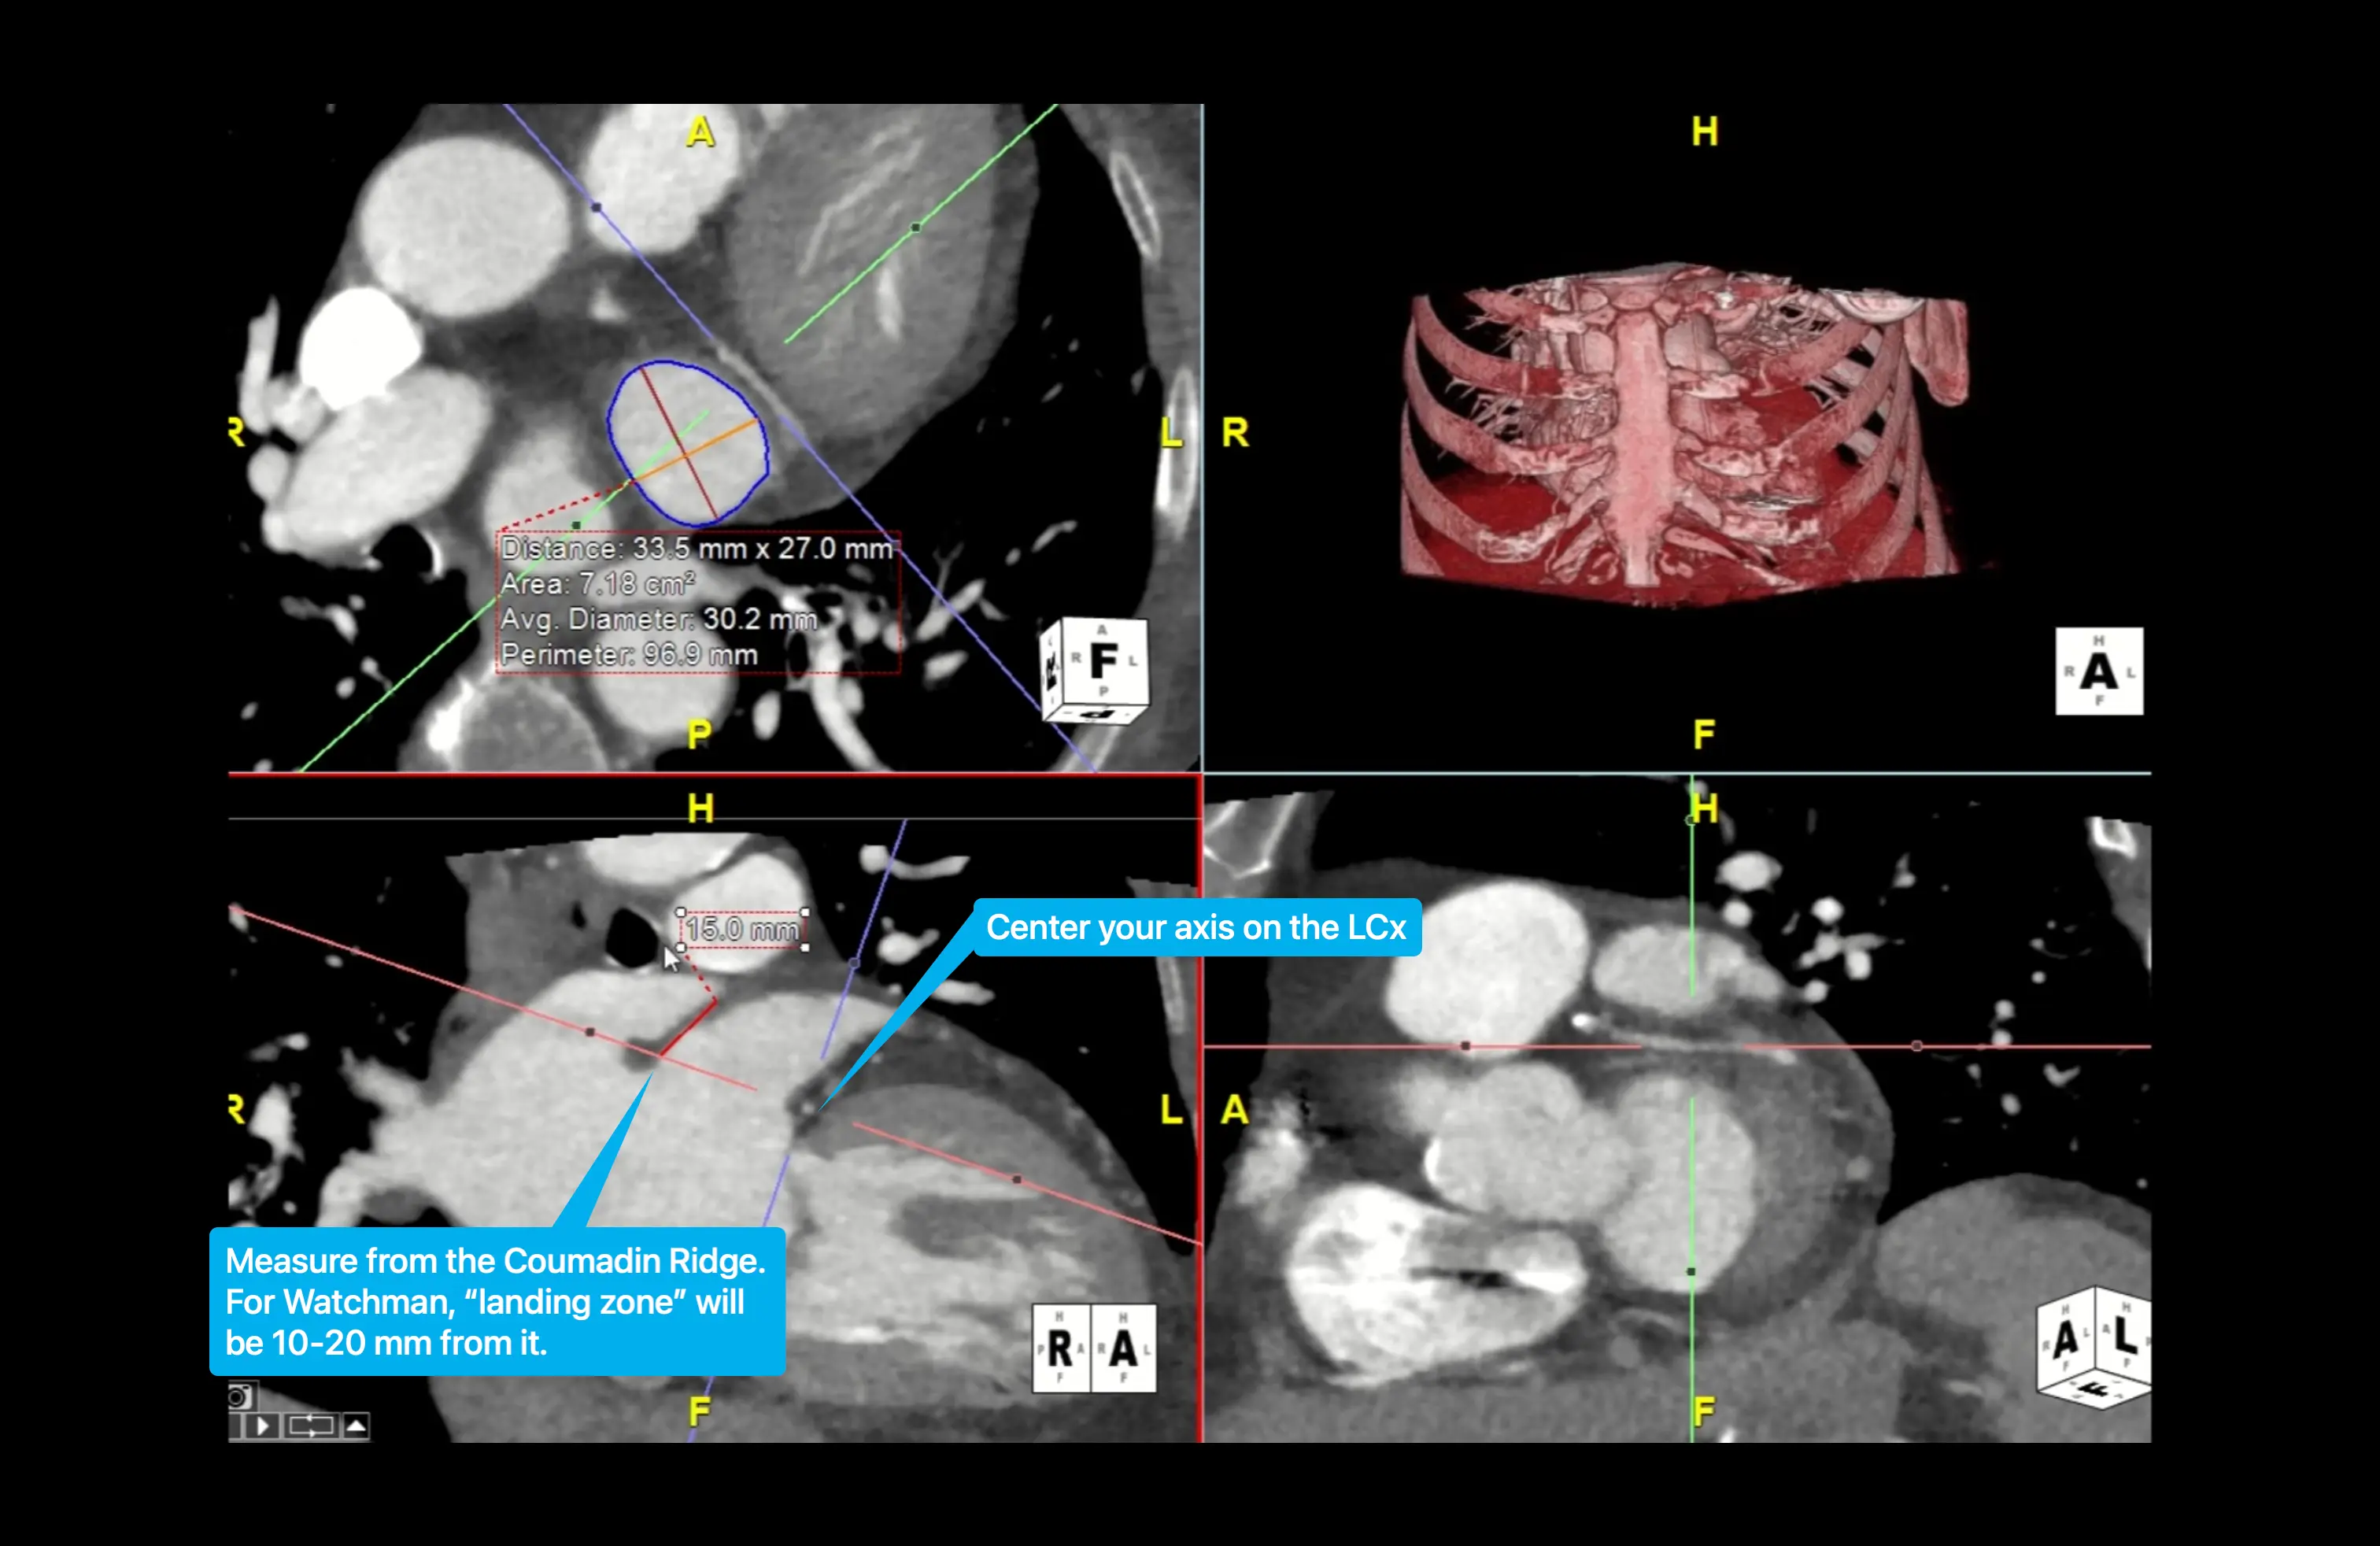

• At CT, the landing zone is identified on the long-axis LAA view. For the Watchman device, the landing zone is located 10–20 mm inside the LAA from the Coumadin ridge (aka limbus). The landing zone diameters for the Watchman device are measured on an en-face-view CT image obtained at a line that connects the LAA adjacent to the left circumflex artery to the point 10–20 mm inward of the Coumadin ridge. 1

• 📝 Movie 3 and 4 from 1 shows how to do this well.